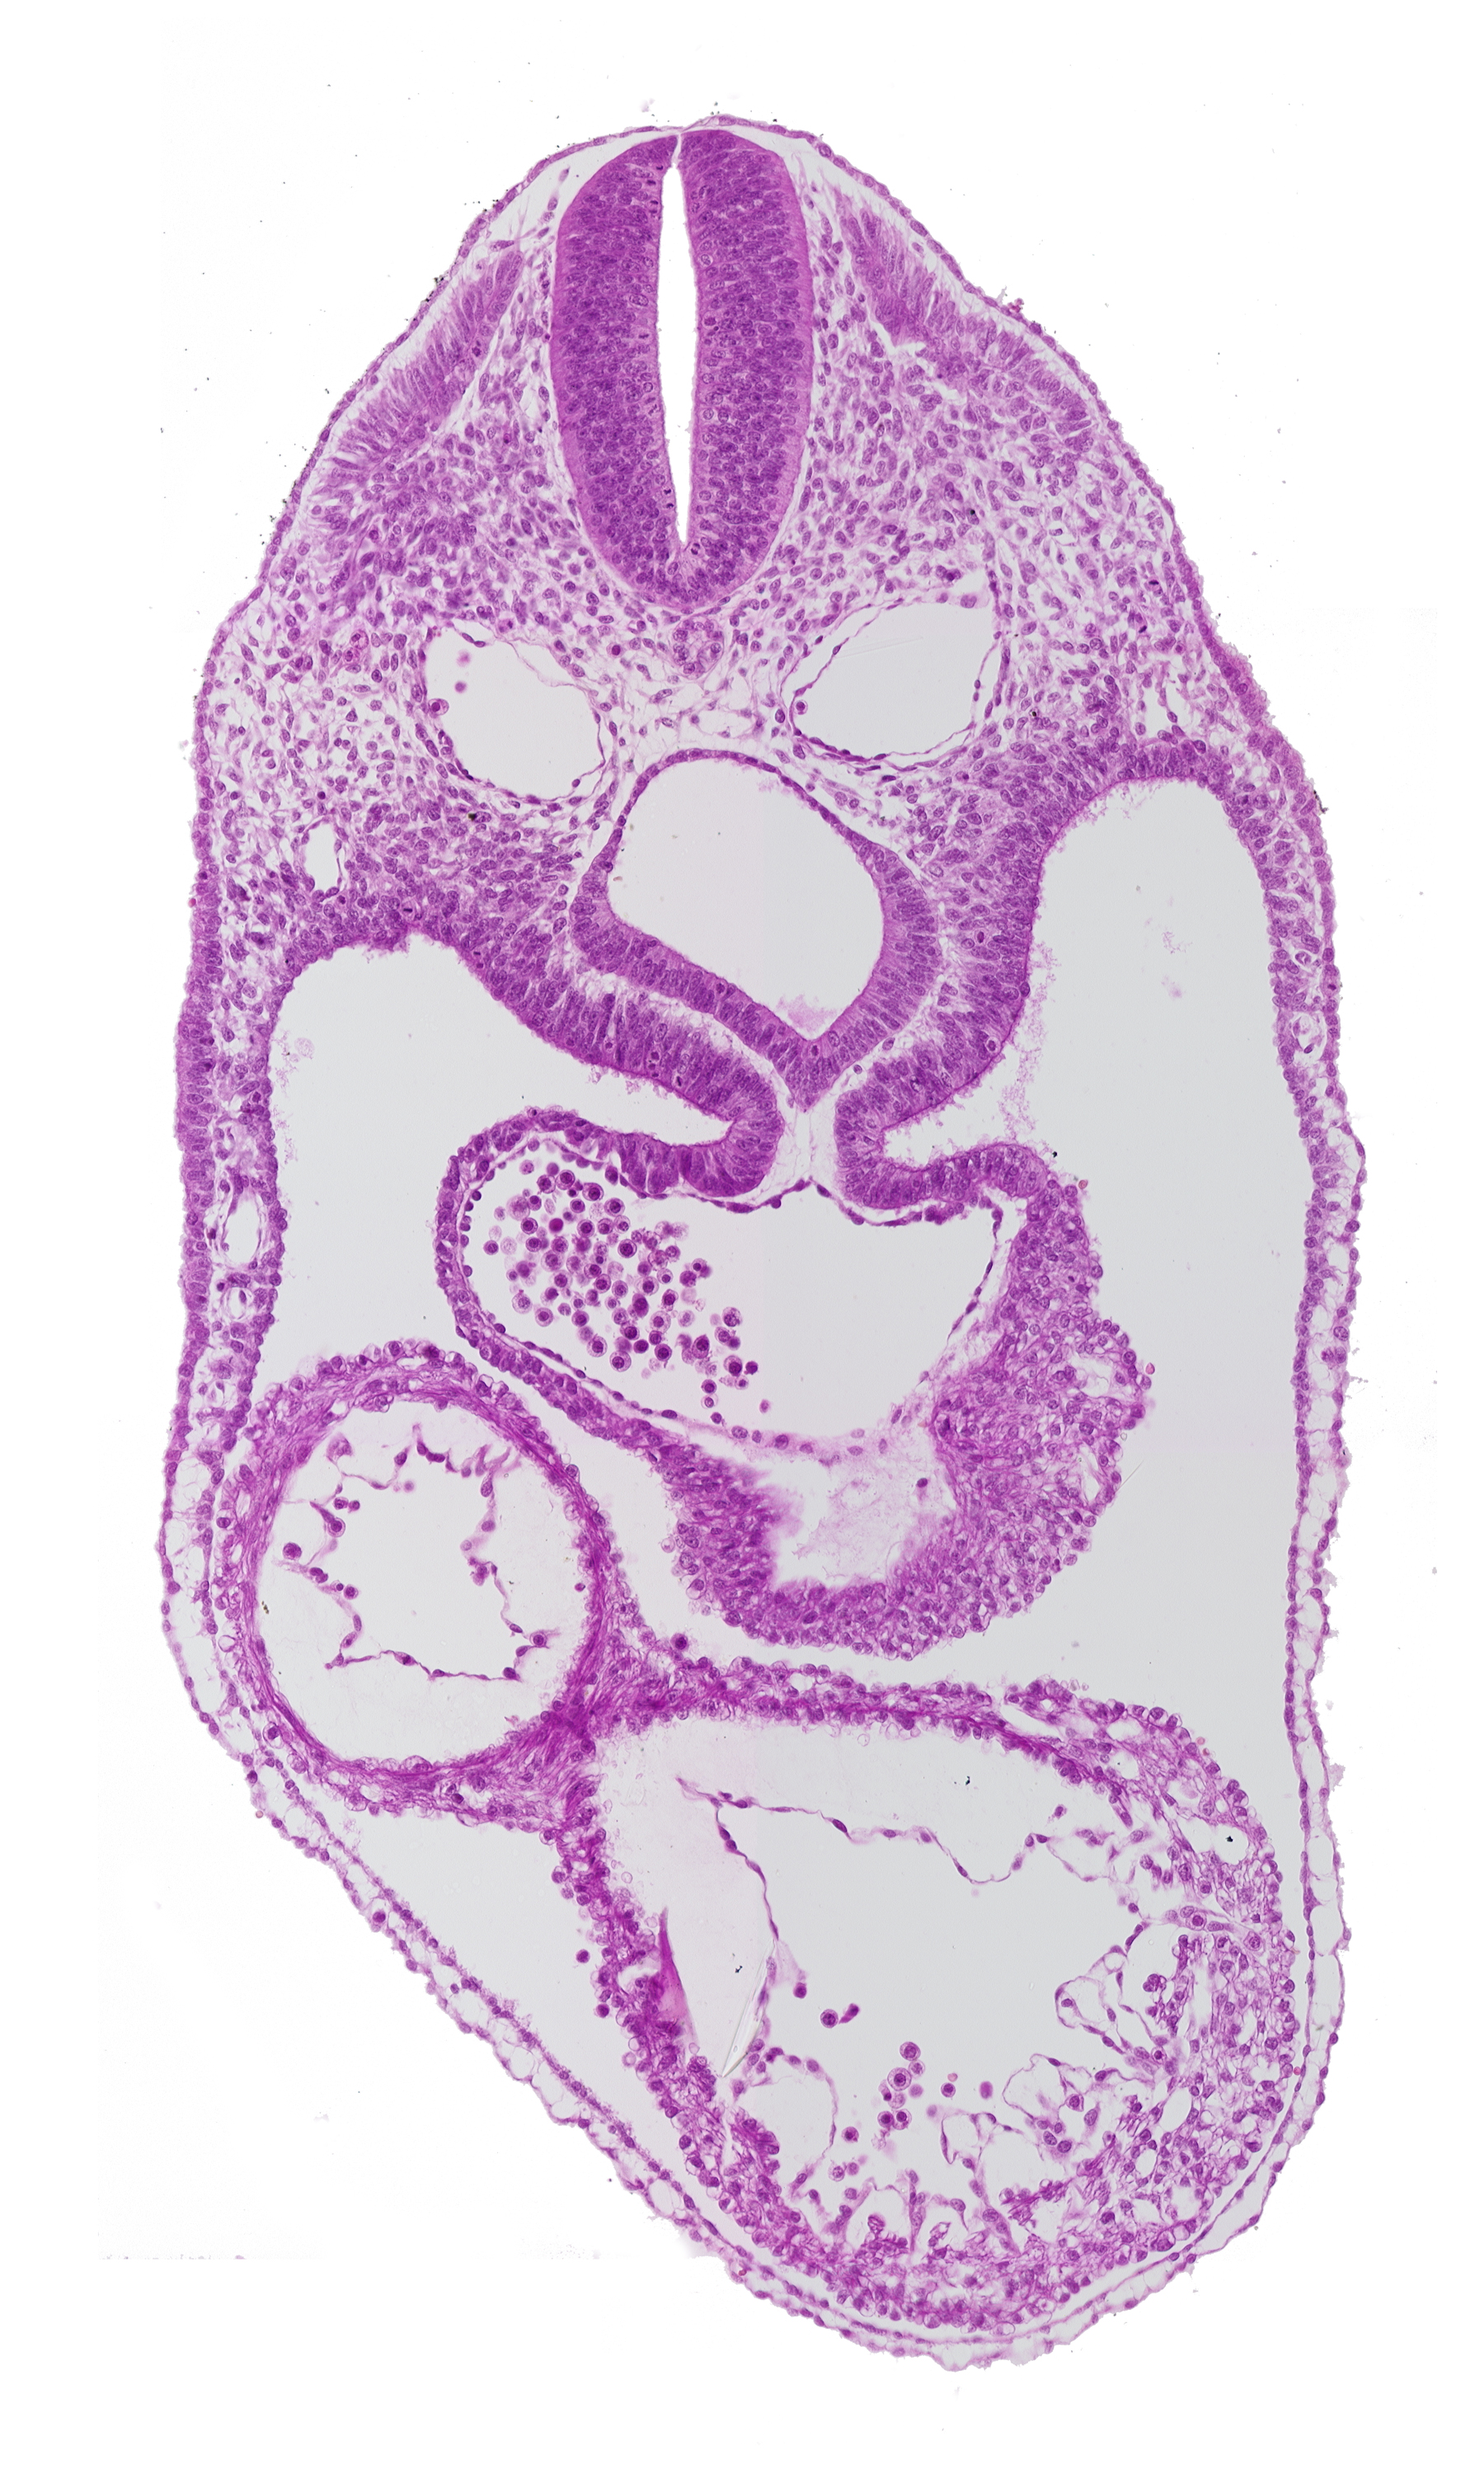

Carnegie Embryo #8943 | Location: 04-03-09

Keywords: anterior interventricular sulcus, cephalic edge of septum tranversum, dermatomyotome 4 (O-4) , dorsal aorta, foregut, junction of common atrium and sinus venosus, laryngotracheal groove, left ventricle, mesocardium, pericardial cavity, posterior interventricular sulcus, precardinal vein, right ventricle

Source: The Virtual Human Embryo.